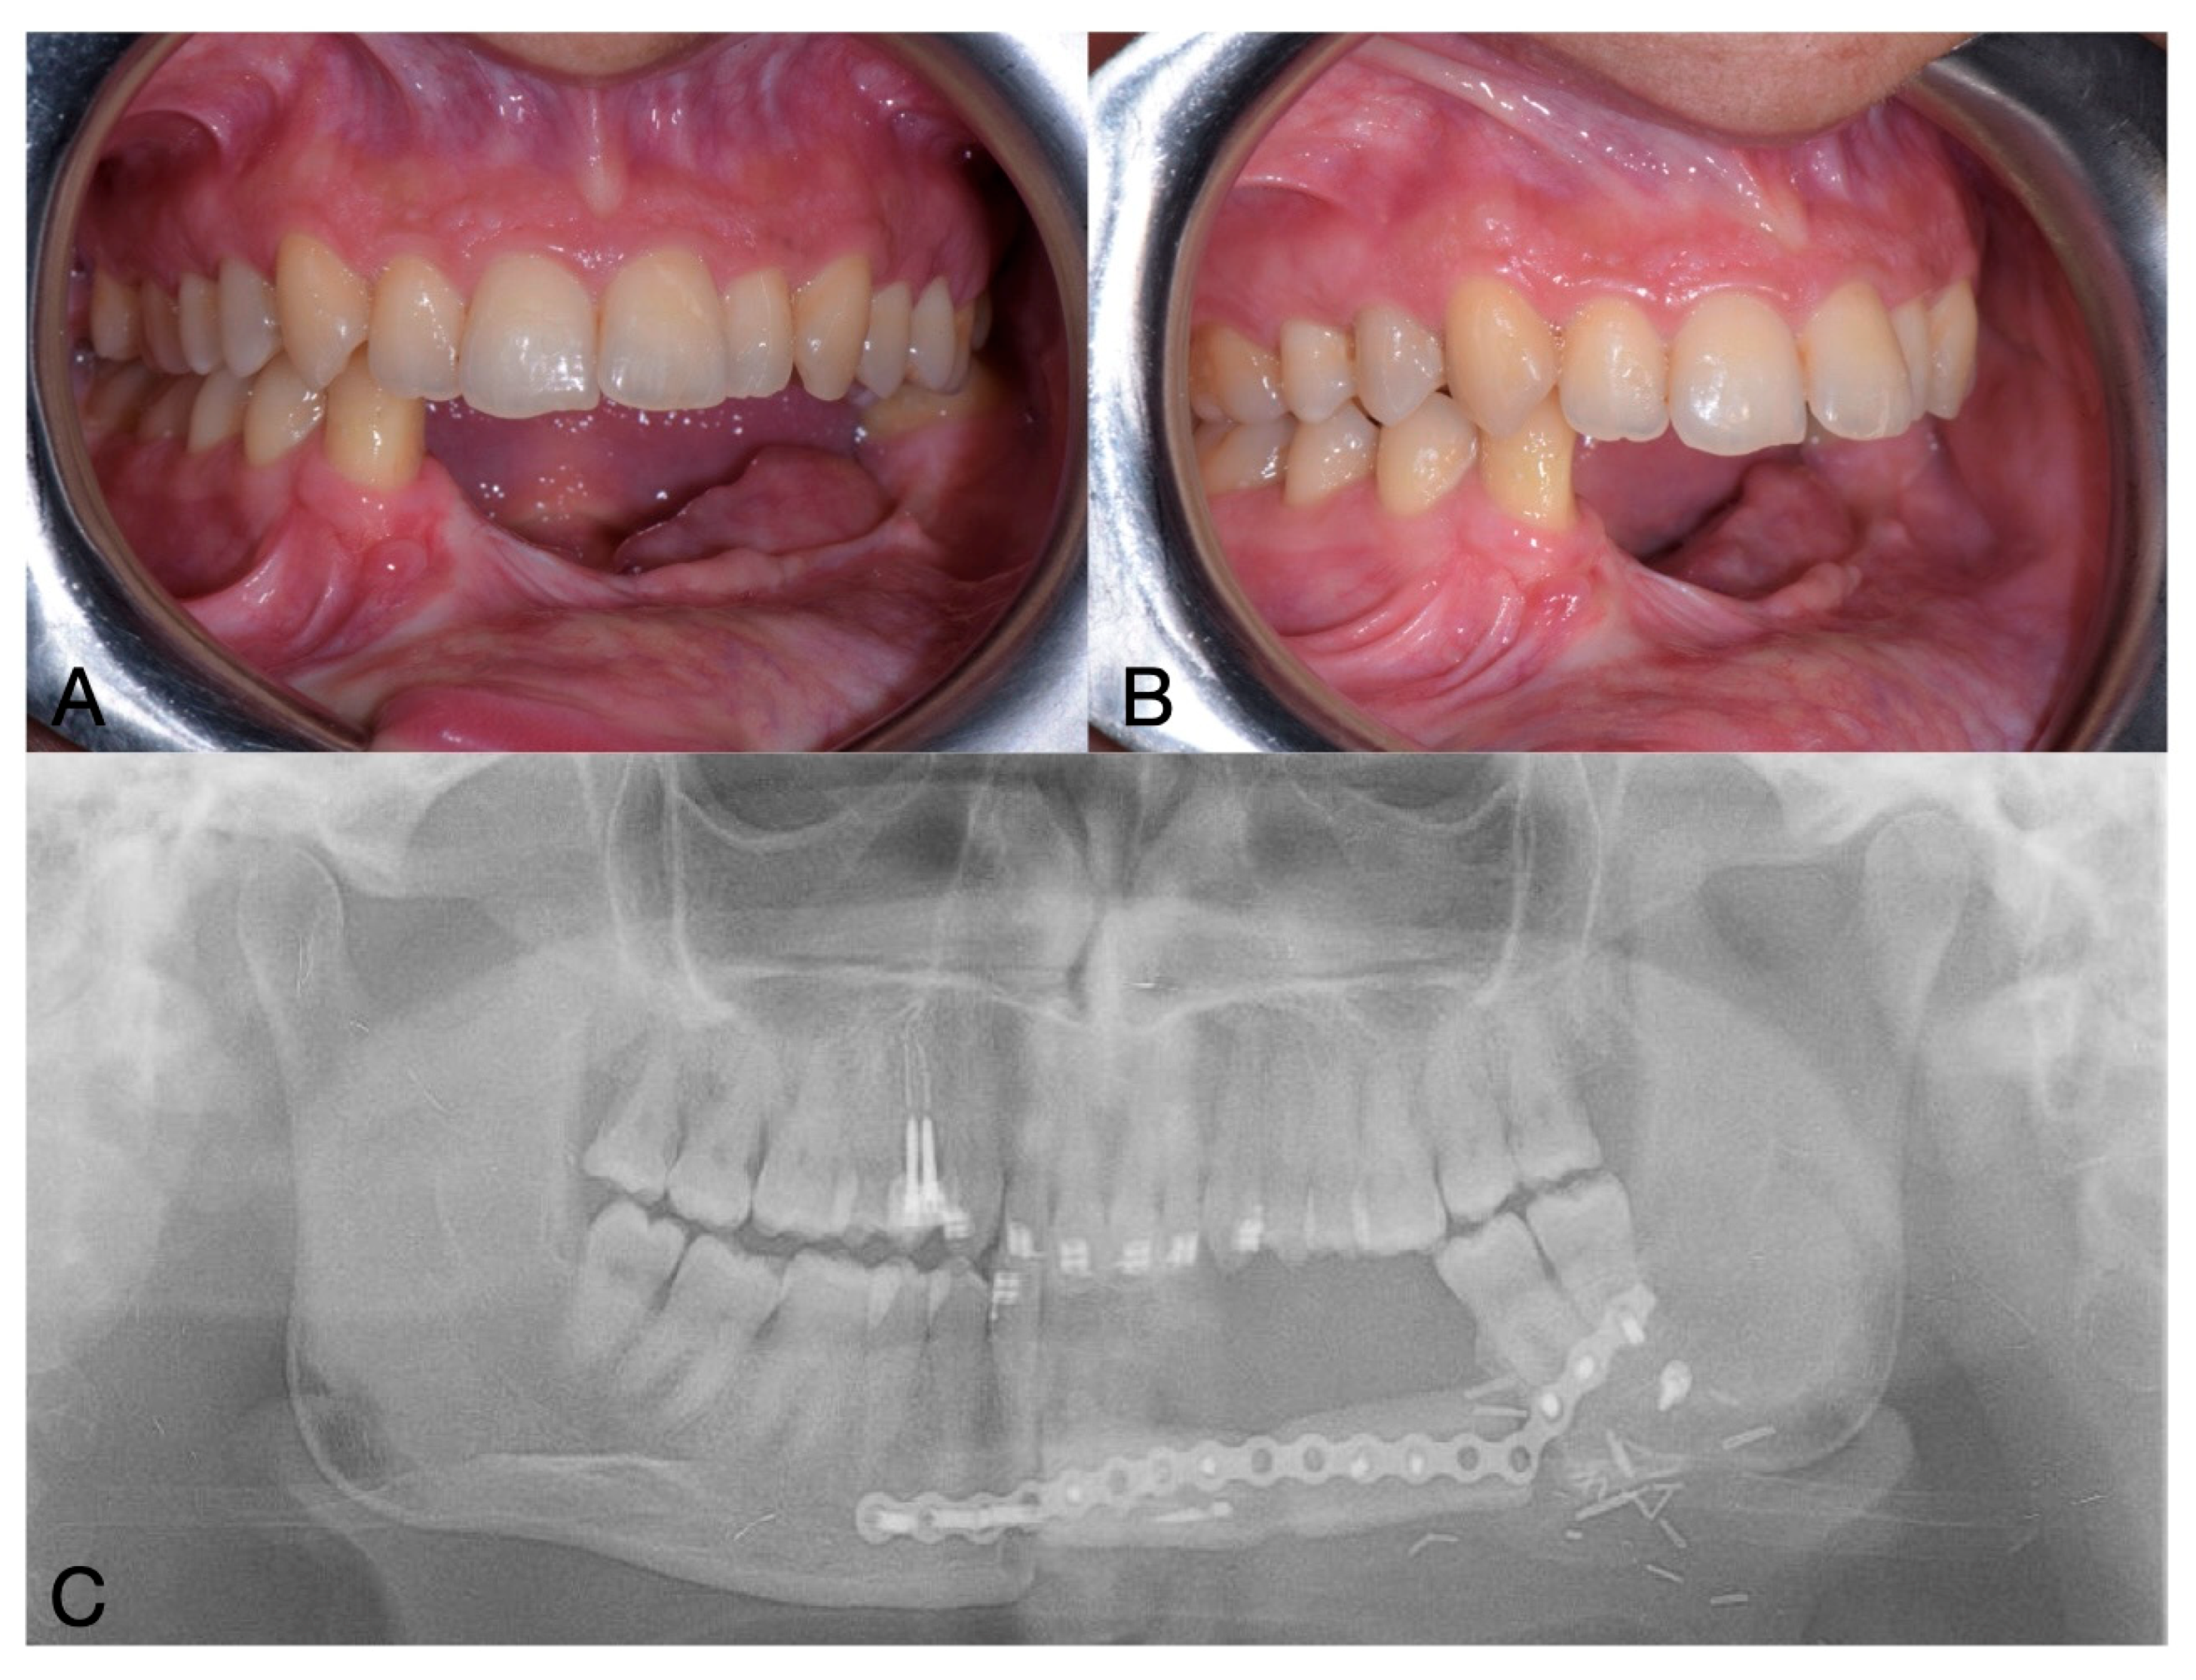

After a 3-month healing period, an OPG was performed, and implant uncovering and soft tissue surgery were planned (Figure 6).

During the second surgery, one implant exhibited absence of osseointegration with no signs of infection and was then removed. Notably, this implant was located near the transition zone between the remaining mandibular bone and the fibula graft, which may have contributed to its failure due to reduced vascularization [21]. An internal connection with a screw-retained abutment was chosen for the prosthetic rehabilitation. Multi-unit abutments (MUAs) were employed to optimize load distribution among the implants. Three MUAs and healing caps were placed, and the flap was apically repositioned to improve buccal fornix depth. The two mesial MUAs had a height of 3.5 mm, whereas the distal one measured 5.5 mm.

The prosthetic rehabilitation was completed four months after implant placement using a bar-retained, metal reinforced resin overdenture. Due to an unfavorable crown-to-root ratio and the loss of one implant, a removable prosthesis was selected—following discussion with the patient—to avoid overloading the remaining implants and to achieve a more favorable distribution of occlusal forces [22]. Furthermore, the decision was supported by the improved ease of oral hygiene maintenance associated with a removable prosthesis.

Analogic impressions were taken with the use of polyether impression material. Performing this prosthetic rehabilitation was challenging because taking impressions on the implants was difficult due to the patient’s limited mouth opening, as the muscles had been cut during the reconstructive surgery of the mandible. With the prosthesis, restoration of masticatory function and improvement in facial aesthetics were observed. The patient experienced a positive impact on her self-esteem and social interactions (Figure 7).

Patient satisfaction was evaluated using a Visual Analogue Scale (VAS) ranging from 0 to 10, assessing both aesthetic and functional outcomes. The patient reported the highest possible score—10 in both categories—indicating maximum satisfaction. Overall, the patient expressed a high level of satisfaction with the treatment outcomes.

Figure 6. Postoperative OPG.

Figure 7. Clinical (A,B) and radiographic (C) situation after prosthetic delivery.